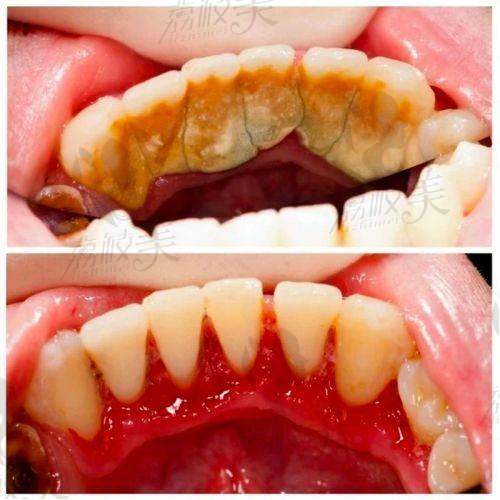

沈阳德立联合口腔医院郑淳奎医生做德国睡眠洗牙实例

在沈阳德立联合口腔医院,有特别多患者都体验过郑淳奎医生的德国睡眠洗牙项目,并且成效都非常不错。有一位张女士,她平时特别注重口腔卫生,但牙齿上还是有一些牙结石,而且她对洗牙非常害怕,之前一直不敢去洗牙。后来在朋友的推荐下,她来到了沈阳德立联合口腔医院,找到了郑淳奎医生。郑医生为她详细介绍了德国睡眠洗牙项目,并根据她的牙齿情况制定了方案。张女士在睡眠状态下完成了洗牙,醒来后发现牙齿变得洁白干净了,而且整个过程没有任何疼痛和不适。她非常惊喜,对郑医生和德国睡眠洗牙项目赞不绝口。还有一位李先生,他的牙齿比较敏感,传统洗牙对他来说简直是一种折磨。在体验了德国睡眠洗牙后,他也感受到了这种洗牙方式的舒适和效率高,牙齿上的污垢被清除得特别干净,而且牙齿敏感的问题也得到了一定的缓解。这些实例都充分证明了德国睡眠洗牙项目的有效性和优越性。